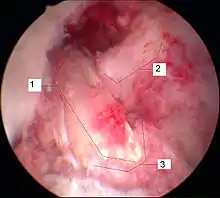

Arthroscopie diagnostique

La sécurité diagnostique la meilleure est obtenue par arthroscopie diagnostique. Ce procédé représente l'étalon-or pour le diagnostic de la rupture de LC. Ce procédé relève d'une chirurgie invasive au minimum, mais comporte certains risques, comme toute intervention chirurgicale dans le genou du patient[113]. Comme cependant le traitement chirurgical d'une rupture de LC sera conduit par chirurgie arthroscopique, il est possible d'enchaîner celle-ci immédiatement après l'arthroscopie diagnostique, par la résection partielle du ligament (pour une déchirure) ou la reconstruction en cas d'arrachement. Avec l'accroissement de la facilité de l'IRM, le nombre d'arthroscopies purement diagnostiques a nettement diminué ces dernières années[114],[115]. L'arthroscopie diagnostique est quand même utilisée comme précédemment comme procédé de choix pour une compréhension certaine du diagnostic de rupture de LC, en cas d'examen clinique confus et d'IRM difficile à interpréter[113].